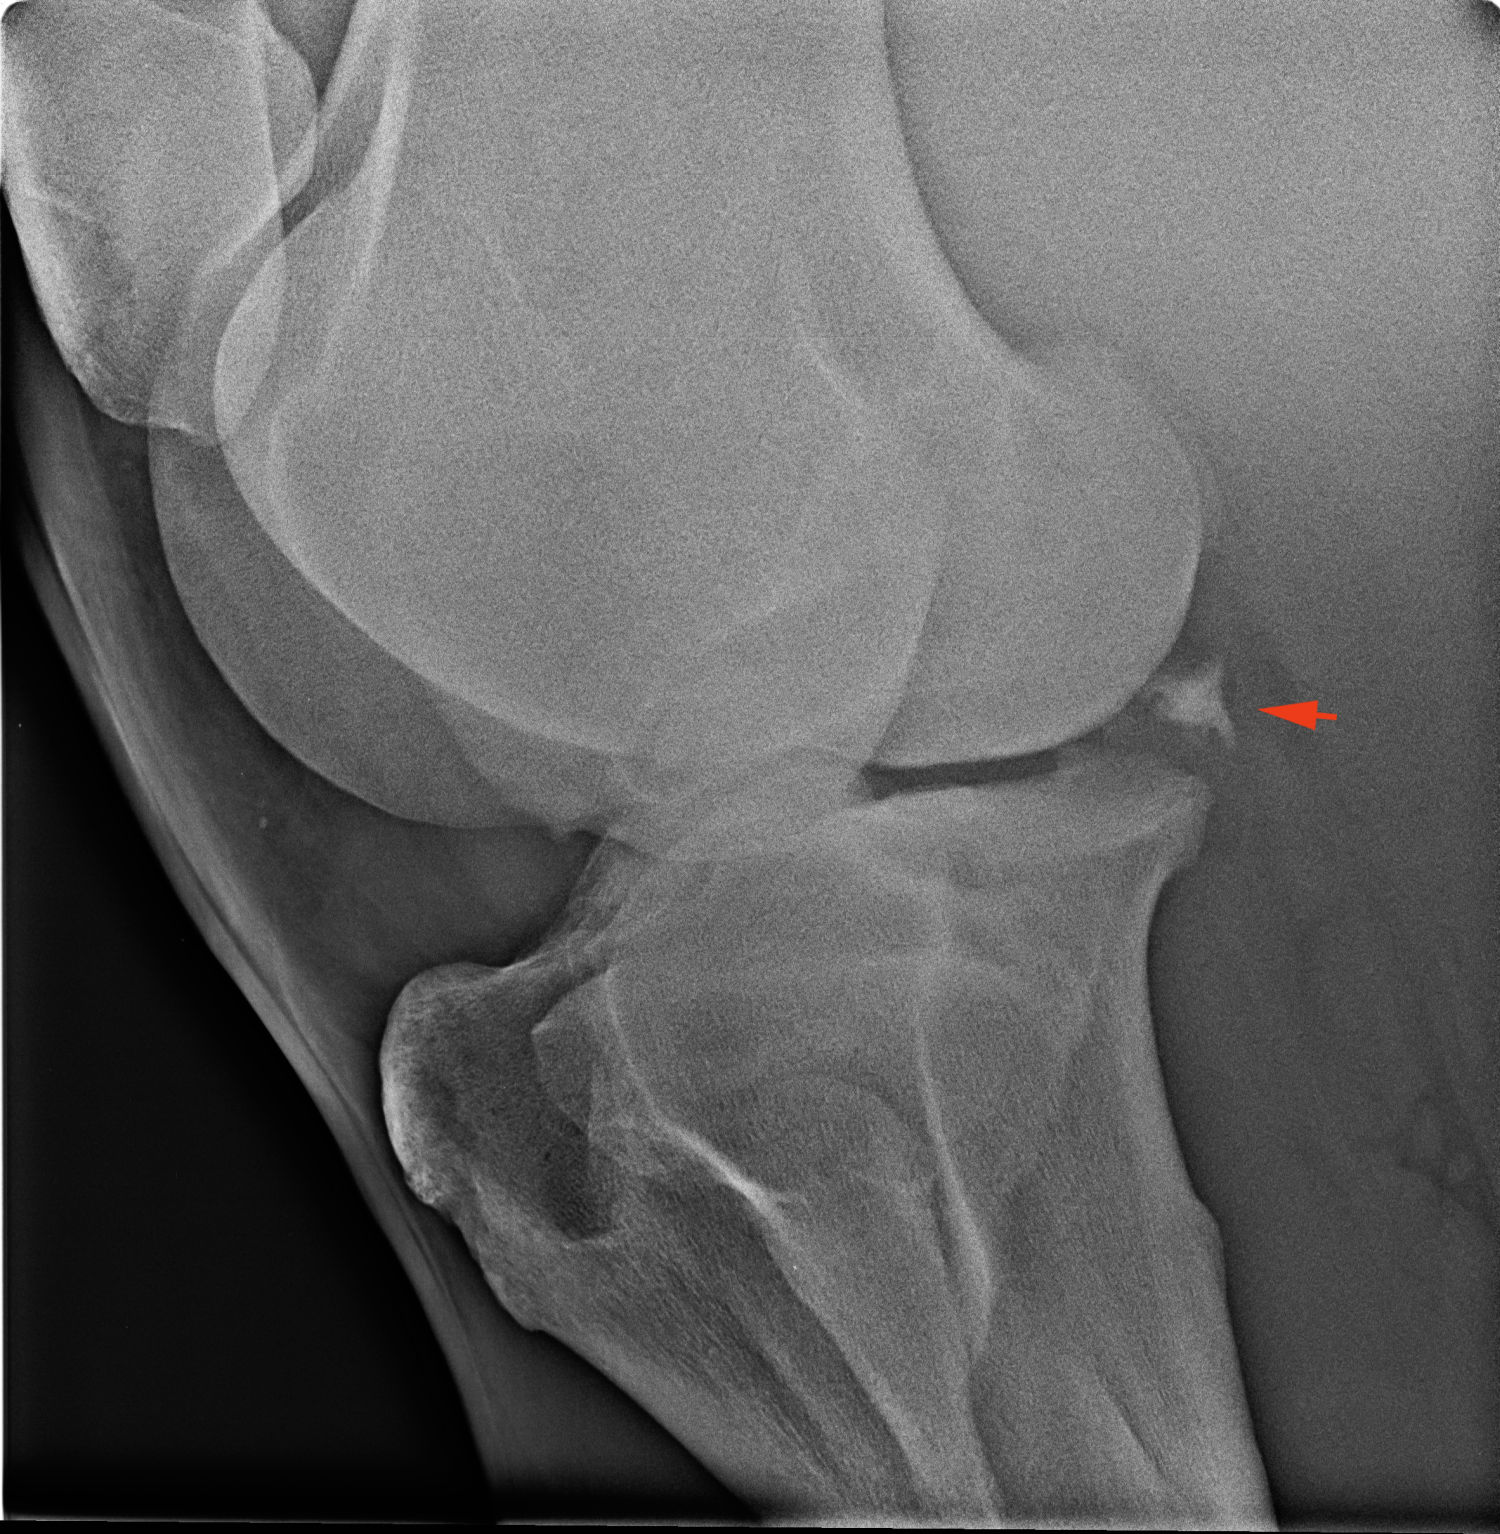

Így néz ki egy egészséges térd RTG felvétele:

A piros nyíl egy meszesedést mutat, ami a c-porc (meniscus) régi megbetegedése miatt alakult ki. Súlyos elváltozás.